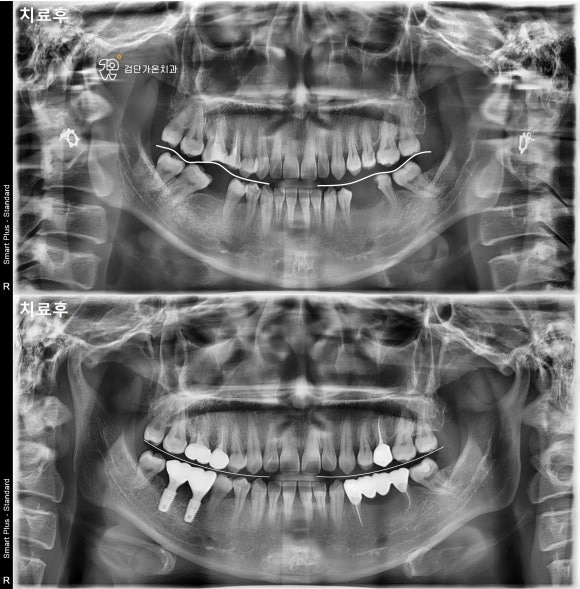

부정교합 치료 전후 파노라마 X-ray(엑스레이)

교합평면 변화 비교 자료

이 검사 자료를 바탕으로 엑스레이와 모형을 분석해 문제점을 정리하고, 개인에게 맞는 치료 계획을 상담을 통해 안내하게 됩니다.

초진에서는 파노라마 엑스레이와 구강 상태 확인 후 대략적인 치료 방향을 안내받고, 정밀검사에서 자세한 기록을 만들어 치료 계획을 확정합니다.

처음 방문하는 초진에서는 치아와 턱 주변을 넓게 촬영하는 파노라마 엑스레이와 구강 상태 확인을 통해,

교정적으로 어떤 문제가 있는지 파악하고 대략적인 치료 방법을 설명드립니다.